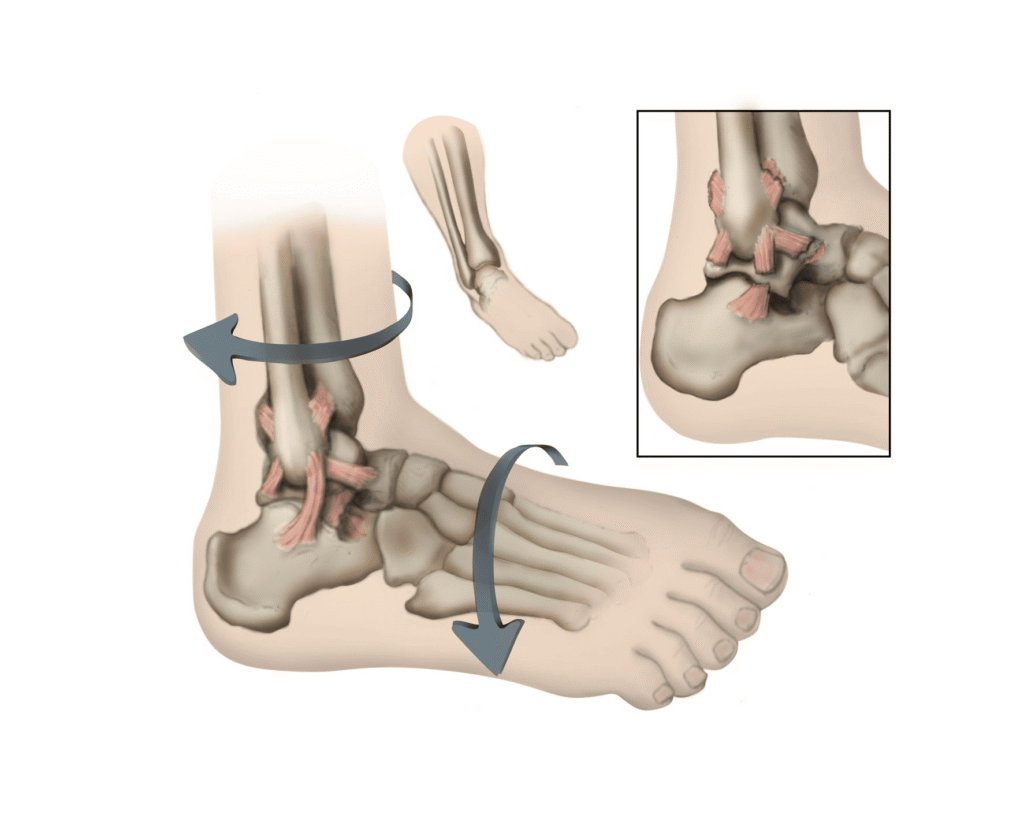

⚙️ 2️⃣ Vad händer biomekaniskt i underbenet

| Struktur | Vad som sker | Konsekvens |

|---|---|---|

| Tibia | Laterala platån har sjunkit (depression 6 mm) → benet lutar utåt | Knäets mekaniska axel flyttas lateralt = valgusaxel |

| Fibula???? | Kan delvis följa med vid diastas → ökad separation i proximala tibiofibularleden | Instabilitet mellan tibia och fibula, ändrad kraftöverföring |

| Mellan tibia och fibula | Diastas (ökat avstånd) → påverkar kanske syndesmosen fibrös, hela vägen ner | Fel rotation och ökad rörlighet i fibula |

| Underbenets rotation | Lateral depression kan ge extern rotation av tibia | Påverkar fotens ställning (pronation) |

| Fotled | Felställd tibia → talus vinklas, foten faller inåt | Valgus-fot / överpronation |

| MCL & LCL | MCL blir uttänjt, LCL förkortat | Instabilitet vid gång och lutning |

Kort sagt:

En breddad, insjunken lateral tibialplatå → valgusfel → yttre sidan ”sjunker” → inre sidan får översträckning → hela underbenet roterar och foten pronerar.

🦶 3️⃣ Vad som händer i foten

När underbenet står i valgus och rotation:

- Foten tvingas kompensera för att du ska kunna stå rakt.

- Det leder till:

- Överpronation (foten faller inåt)

- Inåtrotation av fotvalv och talus

- Smärta i fotled, plantarfascit, peroneus-överbelastning

- Instabilitet i fotleden och ibland smärta vid fibulaspetsen